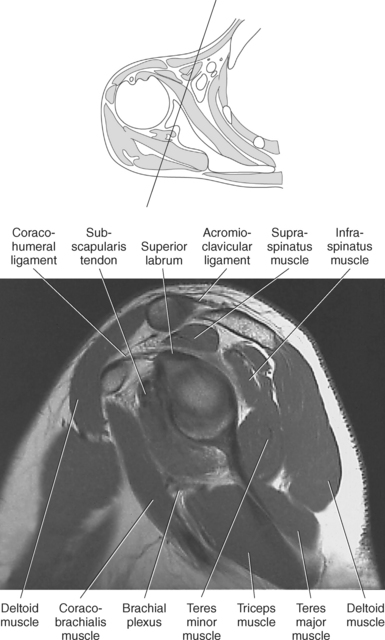

Figure 9.27 Axial, T1-weighted MR scan of shoulder.

Key: c, Clavicle; cc, coracoclavicular ligament; CP, coracoid process; ch, coracohumeral ligament; D, deltoid muscle; H, humeral head; SB, subscapularis muscle; SS, supraspinatus muscle; G, glenoid fossa; L, labrum; ss, supraspinatus tendon; b, tendon of long head of biceps muscle; IG, inferior glenohumeral ligament; mg, middle glenohumeral ligament; sb, subscapularis tendon; T, teres minor muscle.